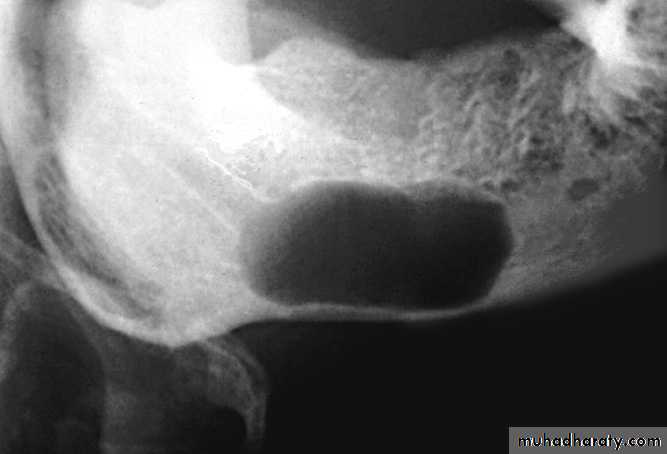

Inferior Alveolar Nerve Canal and Mental Foramen

Superior displacement of the inferior alveolar canal is strongly associated with fibrous dysplasia. Widening of the inferior alveolar canal with the maintenance of a cortical boundary may indicate the presence of a benign lesion of vascular or neural origin within the canal. Irregular widening with cortical destruction may indicate the presence of a malignant neoplasm growing down the length of the canal.